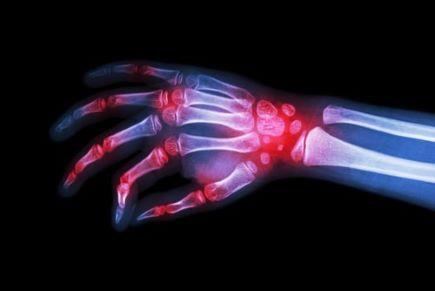

מידע כללי: קבוצת הסטרואידים, משמשת לטיפול במחלות רבות המאופיינות בפעילות דלקתית, למשל במחלות מפרקים, בטרשת נפוצה, במחלות מעי דלקתיות, באלרגיות שונות, באסתמה.

הסטרואידים יכולים לטפל במגוון מצבי דלקת, גם במצב של התלקחות דלקת, ולכן משמשים גם במצבים התקפיים בדלקת במחלות כרוניות (למשל אצל חולי קוליטיס, חולי טרשת נפוצה וחולי אסטמה).

הסטרואידים פועלים כנגד תהליך דלקתי בגוף, מדכאים את מערכת החיסון, מביאים לירידה בייצור ההורמון הטבעי קורטיזון.